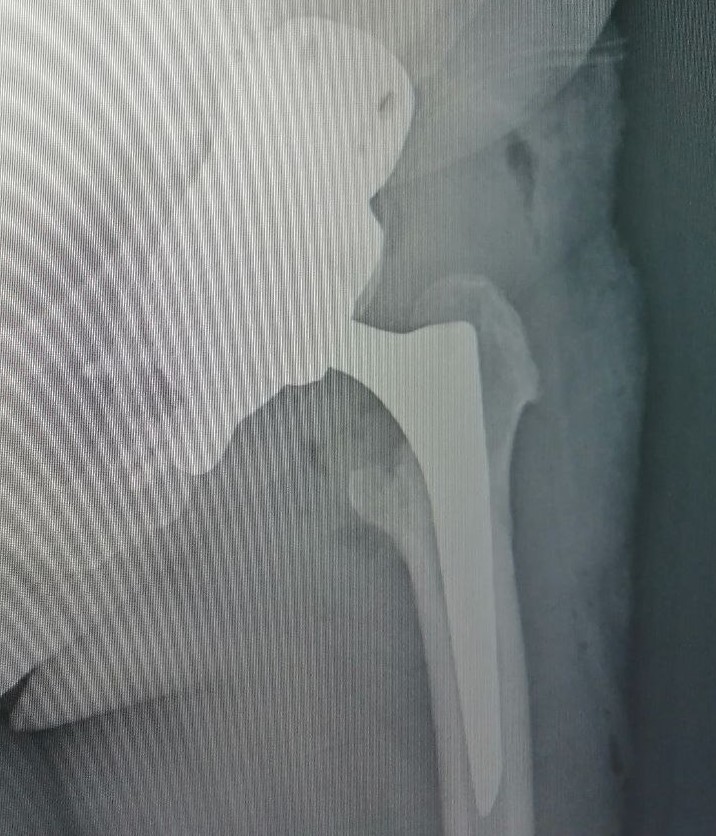

По КТ-снимкам 3D-принтер напечатал точную копию поврежденной тазовой кости. Затем был смоделирован фрагмент для замещения дефекта. Его выполнили в двух вариантах: из полимерного материала – для пробной примерки и из титана – для окончательной установки. Во время хирургического вмешательства 3D-эндопротез идеально встал на своё место. Заместив разрушенный участок кости титановым «двойником», травматологи-ортопеды смогли приступить к следующему этапу лечения – эндопротезированию всего тазобедренного сустава. Через сутки пациентка уже вставала на ноги с помощью дополнительной опоры, а сегодня под контролем инструкторов-методистов ЛФК разрабатывает новый сустав при ходьбе.